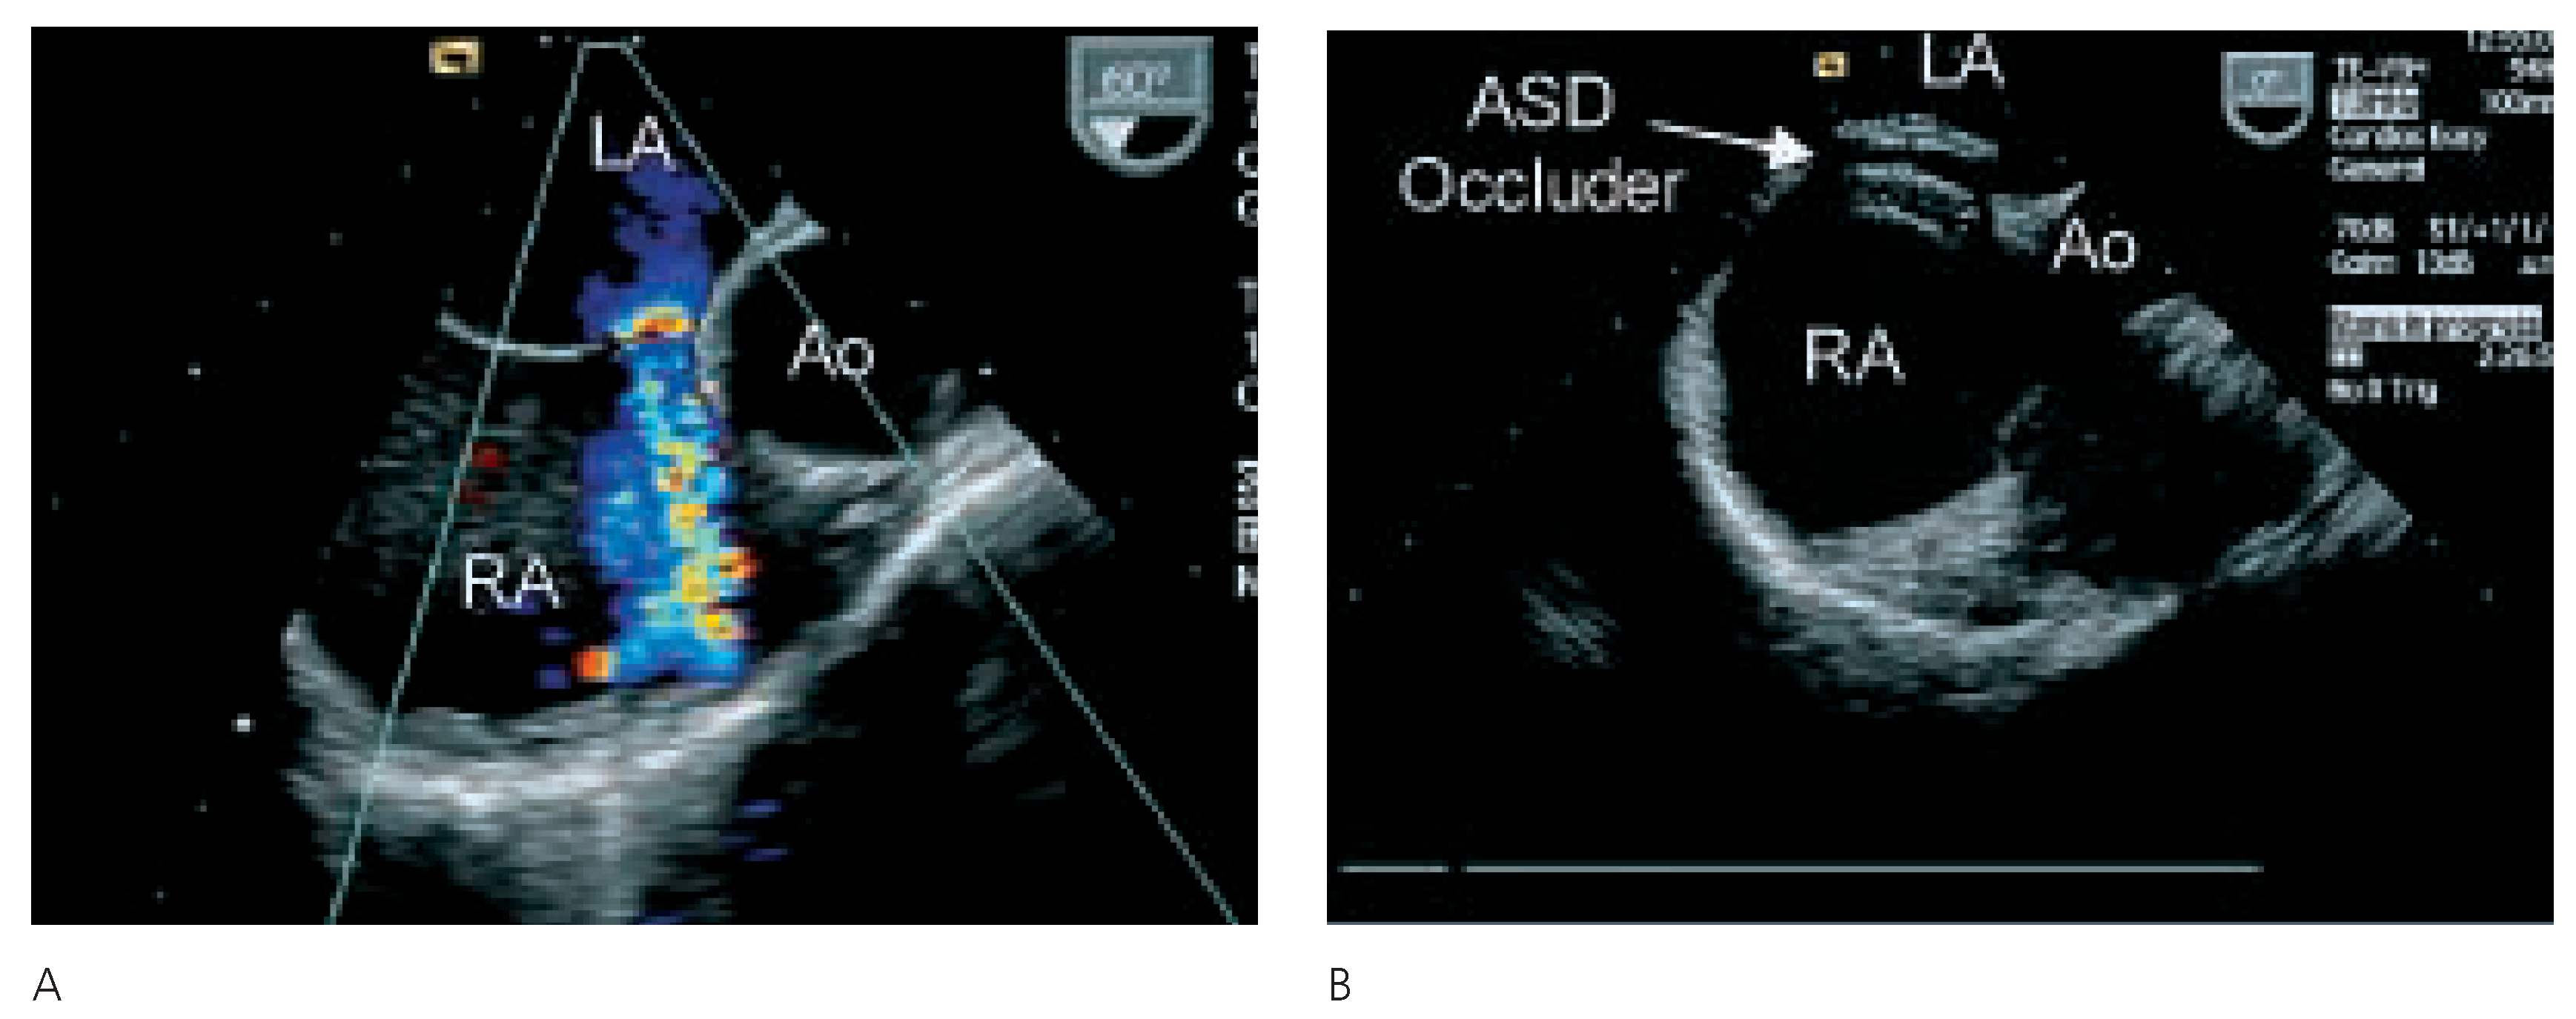

Nach eingehender Diskussion der Befunde mit allen involvierten Kollegen, der Patientin und ihren Angehörigen wurde die Patientin zum perkutanen Verschluss des ASD an die Kardiologie des UniversitätsSpitals Zürich überwiesen. In der invasiven Herzkatheteruntersuchung konnte eine koronare Herzkrankheit und eine pulmonal-arterielle Hypertonie ausgeschlossen werden. Der mittlere pulmonal-arterielle Druck betrug 19 mm Hg und der pulmonale Widerstand 81 dyn×sec×cm–5. Vor Verschluss des Vorhofseptumdefektes, welcher in Narkose und unter transösophagealer Überwachung durchgeführt wurde, konnte oxymetrisch kein Rechts-Links-Shunt nachgewiesen werden. Der Links-Rechts-Shunt betrug unter diesen Bedingungen zudem auch nur 14%. Nach Sondieren des Vorhofseptumdefektes wurde mittels Messballon eine ASD-Grösse von 19 mm gemessen. Es wurde ein Amplatzer-ASD-Occluder® 20 mm im Vorhofseptum plaziert. Aufgrund der Lokalisation des ASD mit praktisch fehlendem Saum gegen die Aorta kam der Schirm nahe der Aortenwurzel zu liegen (Figure 3 and Figure 4). Die orale Antikoagulation wurde in der Folge abgesetzt und als Nachbehandlung erhielt die Patientin 100 mg Aspirin® und 75 mg Plavix® für drei Monate, gefolgt von Aspirin® 100 mg für weitere drei Monate. Ebenfalls wurde für sechs Monate eine Endokarditisprophylaxe durchgeführt. Nach dem Eingriff war die Anstrengungsdyspnoe praktisch behoben und die transkutane Sauerstoffsättigung betrug nun im Stehen und unter Belastung immer über 90%. In der transthorakalen Echokardiographie sechs Monate nach dem Eingriff konnte kein Shunt auf Vorhofebene mehr nachgewiesen werden. Der Amplatzer-Occluder lag in regelrechter Position. Weiterhin war der systolische pulmonal-arterielle Druck nicht erhöht.

Figure 4.

A Ausmessen der ASDGrösse mittels Ballon. B Kontrolle der AmplatzerOccluder-Lage mittels TEE. C Amplatzer-Occluder in Position.